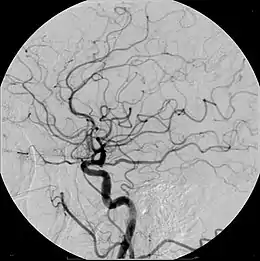

Un medio de contraste es cualquier sustancia que se usa para mejorar la visibilidad de estructuras o fluidos dentro del cuerpo. Un ejemplo de esto son los líquidos opacos a la radiación que se utilizan durante un diagnóstico de rayos X, para resaltar las características que hay de un tejido a otro.[1]

Se administran por las vías en que mejor se distribuyen por la estructura a ser examinada, ya sean ingeridos o por enema en el caso del tracto digestivo, inhalados para las vías respiratorias o inyectados para visualizar los vasos sanguíneos, órganos y tejidos.